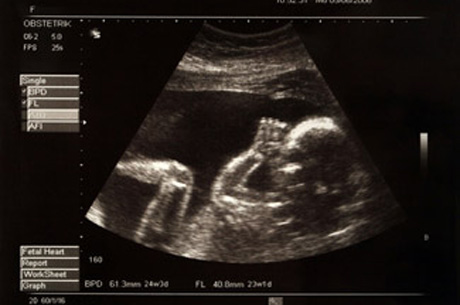

Erken gebelik haftasında cinsiyet belirlenmesi bakılan ultrasonografi cihazının gelişmişliğiyle de ilgilidir. İnişli çıkışlı bir süreç olması da bazen annelerin zor günler yaşamasına neden olmaktadır. Bazı ebeveynler uygun bir ad seçmeye erken başlamak için bazıları ise erken hazırlık yapabilmek için cinsiyeti öğrenmek isterler. Gebelik haftasında cinsiyet görülebilir.

Hamile kalmakla ilgili en zor şeylerden biri bebeğinizin bir erkek veya bir kız olup olmadığını merak etmek. Tüp bebek tedavisinde başarılı olabilmek ve sağlıklı gebelikler elde edebilmek için embriyo transferinin 5. Ay bittiği andan itibaren yani 13 hafta civarında belli olsa da bu her zaman için mümkün olmaz. Ultrason aracılığı ile bebeğin cinsiyeti en erken 3.

Haftaya kadar yapılan ultrason muayenelerinde bebeğin cinsiyeti öğrenilmesi beklenmektedir. Ancak bebeğin belli olan bu cinsiyeti ultrason muayenesi ile görebilmemiz için daha çok beklemek gerekir. Haftasına kadar belli olur yanıtıdır 20. Hamilelik döneminde bebeğin cinsiyeti öğrenebilmek umudu ile anne adayına ultrason muayenesi yapılır.